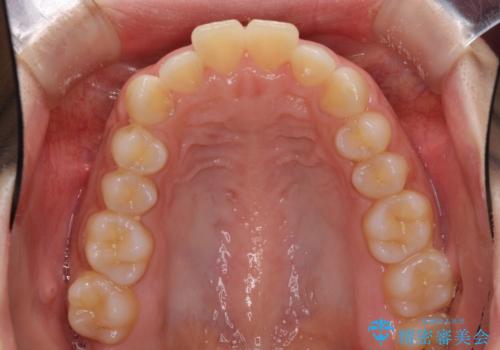

- 口元の突出感と口の閉じにくさを気にして来院された患者様です。

上下左右の小臼歯4本を抜歯し、ワイヤー装置にて口元を引っ込めるよう矯正治療を行うこととしました。

上下顎ともに前突しており、特に上顎は著しい突出感でした。

また、下顎歯列には左右差があり、非対称な抜歯が必要と判断されたため、治療は困難なものとなりました。